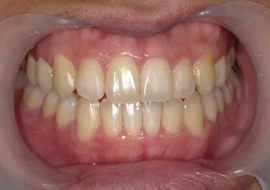

症例4

Before

After

| 主訴 | 上下前歯のがたつき |

|---|---|

| 年齢 | --- |

| 治療 期間 |

約9ヶ月 |

| 治療 内容 |

インビザラインiGoで上下顎の治療。 |

| 治療費 | ¥550,000(税込)/調整料含む |

| 治療のリスク | 矯正終了後は、リテーナーを指示通りに使用し、歯の後戻りを防ぐ必要があります。 |